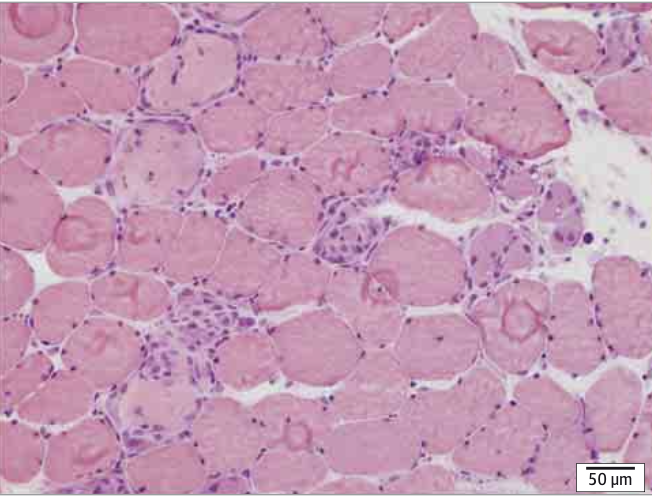

筋生検では全例に壊死と再生が確認され、22%に軽度の炎症浸潤がみられました。ただし多発性筋炎と異なり、非壊死線維への炎症細胞侵入は認められず、病態が「壊死中心」であることが再確認されました。病理学的にはマクロファージの浸潤が主体であり、獲得免疫よりも自然免疫系の関与が大きい可能性が指摘されます。